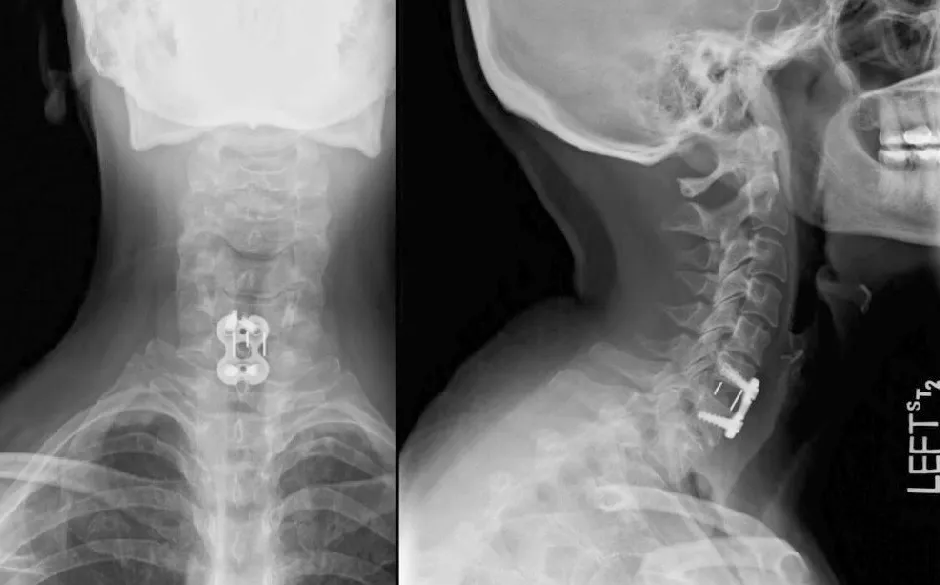

W dalszym etapie przeprowadzane są badania obrazowe, takie jak rentgen, tomografia komputerowa (CT) lub rezonans magnetyczny (MRI). Te metody pozwalają na dokładną ocenę stanu tkanek oraz struktur kostnych w okolicy szyi.